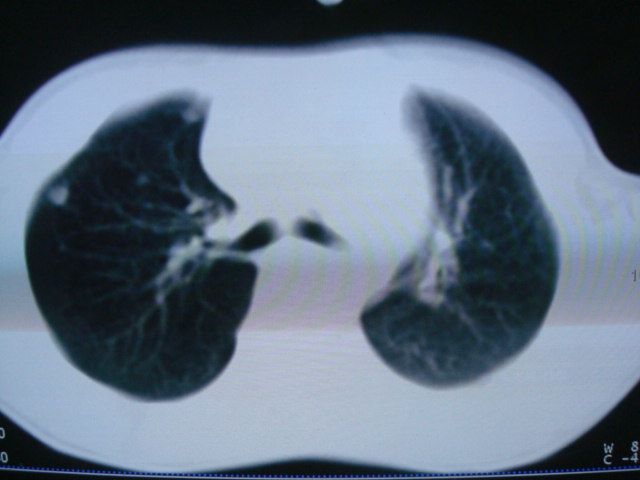

标题: PED0869:男,10岁,肺内多发结节+胸水

男,10岁,左胸痛,发热轻,血象高。后到省级权威医院治疗,病情明显好转,结果几天后公布。老机器,图像质量差,见谅。